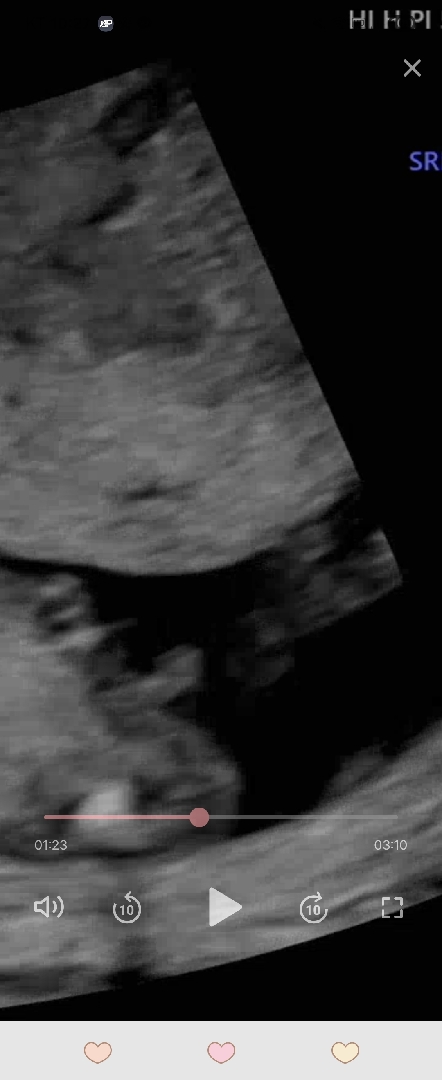

이게성기일까여?

전 성기로 보여서요..... 14주1일이였어요...

돌기!각도는 아들로보여욥